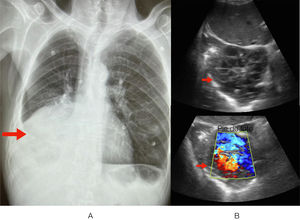

Un paciente de 56 años de edad, de origen rumano, consultó por dolor abdominal localizado en el hipocondrio derecho y vómitos con intolerancia a la vía oral. En el interrogatorio dirigido refirió síndrome constitucional en los últimos meses. En el examen físico se objetivó una llamativa caquexia, así como hipofonesis basal derecha y dolor a la palpación abdominal. Se realizó inicialmente una radiografía de tórax, que mostró atelectasia en el pulmón derecho (fig. 1A), lo que llevó a realizar una ecografía clínica, que reveló una formación tumoral tabicada en contacto con el pericardio, así como una consolidación posiblemente debida a una atelectasia obstructiva (fig. 1B). Se completó el estudio mediante una TC torácica que confirmó la presencia de una masa endoluminal, sugestiva de un proceso neoproliferativo (fig. 2).